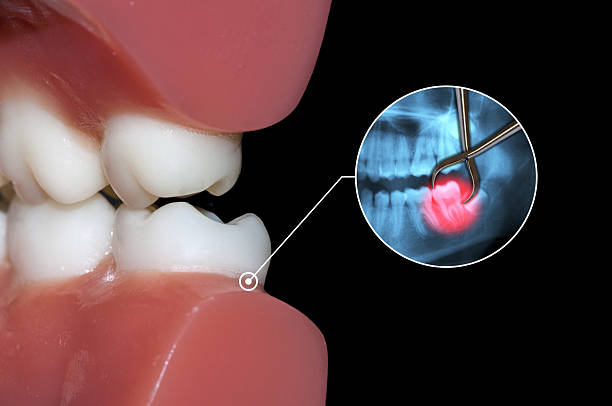

ฟันคุดคือ ฟันกรามซี่ในสุด ทั้งหมด 4 ซี่ บน ล่าง ซ้าย ขวา ไม่สามารถขึ้นได้ตามปกติเพราะพื้นที่ไม่เพียงพอให้ฟันสามารถขึ้นมาได้ บางซี่อาจจะโผล่ขึ้นมาเล็กน้อย และบางซี่ถูกฝั่งอยู่ในกระดูดขากรรไกร อาจจะขึ้นตรง เอียงหรือนอนในแนวราบส่วนใหญ่ฟันคุดมักพบว่าอยู่ที่ฟันกรามซี่ล่างในสุดและพบมากสุดในช่วงอายุ ประมาณ 16 – 25 ปี หรืออาจจะช้ากว่านั้น